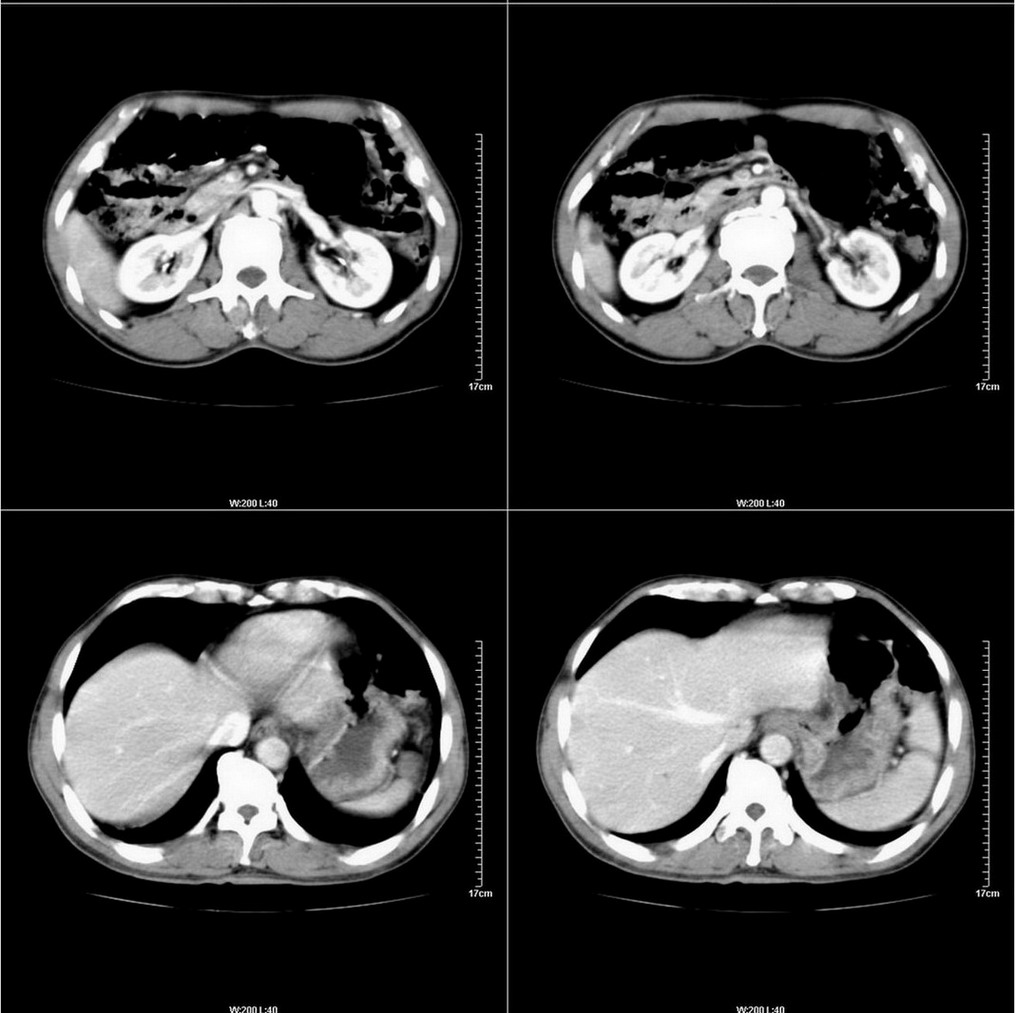

标题: CT14220:男性,59岁。腹部疼痛不适半年余。 [打印本页]

标题: CT14220:男性,59岁。腹部疼痛不适半年余。

看着胆囊周围不舒服。

建议结合胃镜或钡餐检查,考虑胃底贲门癌可能性大。